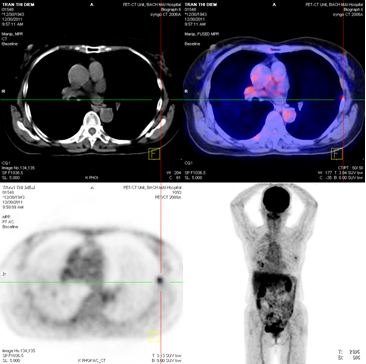

Chụp PET/CT:

Hình 4: Hình ảnh PET/CT có khối u thùy dưới phổi phải 2,6 × 2,8 cm, Max SUV= 5,32

Hình 5: Hình ảnh PET/CT có tổn thương cung sau xương sườn số 5 bên trái, và khối u não vùng đỉnh trái

Chụp PET/CT toàn thân sau 6 tháng điều trị:

Trước điều trị : Khối u thùy dưới phổi phải 2,6 × 2,8 cm, Max SUV = 5,32

Sau điều trị 6 tháng: U tan gần hoàn toàn

Hình 7: Hình ảnh PET/CT toàn thân sau 6 tháng điều trị: Khối u phổi tan hoàn toàn